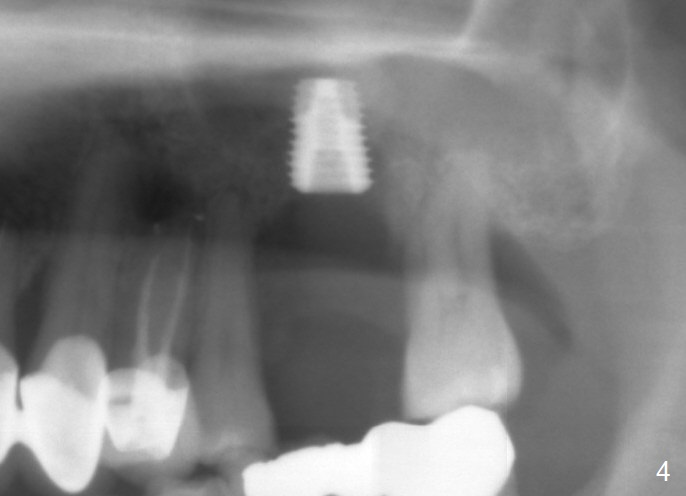

When the tooth #14 is extracted, the buccal plate is lost, while the apex of the palatal socket is perforated. The palatal slope of the septum appears to be a suitable site for osteotomy, but the depth seems to be 2 mm. After sequential osteotomy until 5.3 mm with drills, a 5.9 mm SM tap obtains stability (Fig.2). A 5.9x8 mmm implant is placed with barely sufficient stability after 1 piece of PRF membrane and VeraGraft (Fig.2-4). The implant rotates and dislodges when an abutment is being placed. Neither do 6-8x17 mm Tatum taps achieve primary stability. Socket preservation is performed, followed by periodontal dressing (Fig.5). Primary stability might have been obtained if a smaller IBS implant with fins were placed in the palatal socket. The periodontal dressing has dislodged 1 week postop; the socket appears healing (Fig.6,7). Bone graft seems to be minimal or bone density of the graft is low (Fig.8). The socket heals with a wide ridge 2 months post socket preservation, but the tooth #15 seems to be buccal (Fig.9) and mesial (Fig.10) shift. After use of Magic Split and Expanders (until 3.8 mm for 13 mm), try 5 mm dummy implant (Fig.11). If 6 mm one fails to achieve stability substantially, switch to 7 mm Tatum tapered tap provided there is enough mesiodistal space (use 8 mm implant positioner to gauze the space beforehand (preop)). Consider using Vanilla (not Vera) Graft to fill in the gap between implant and osteotomy. When primary stability is obtained, place a nonfunctional provisional to prevent further shifting (Fig.11 white outline). After osteointegration, use the provisional (reline and separator) to distalize the tooth #15.